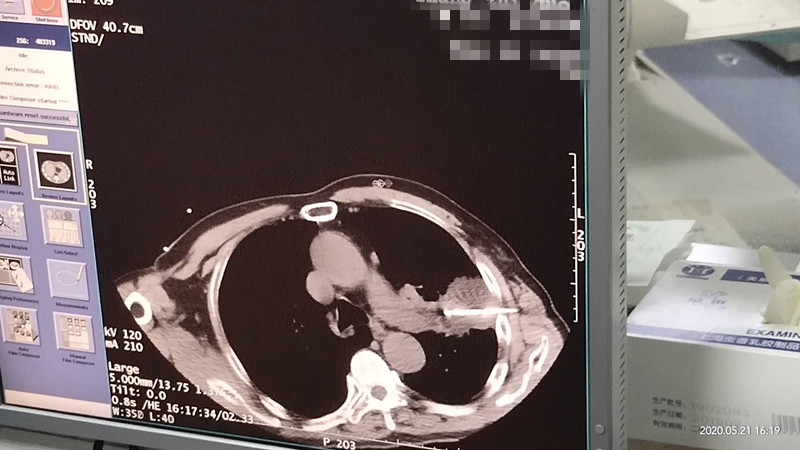

76岁肺部氩氦刀冷冻消融

发布人:美国氩氦刀技术官方网站    发布时间:2020/5/22 15:12:45